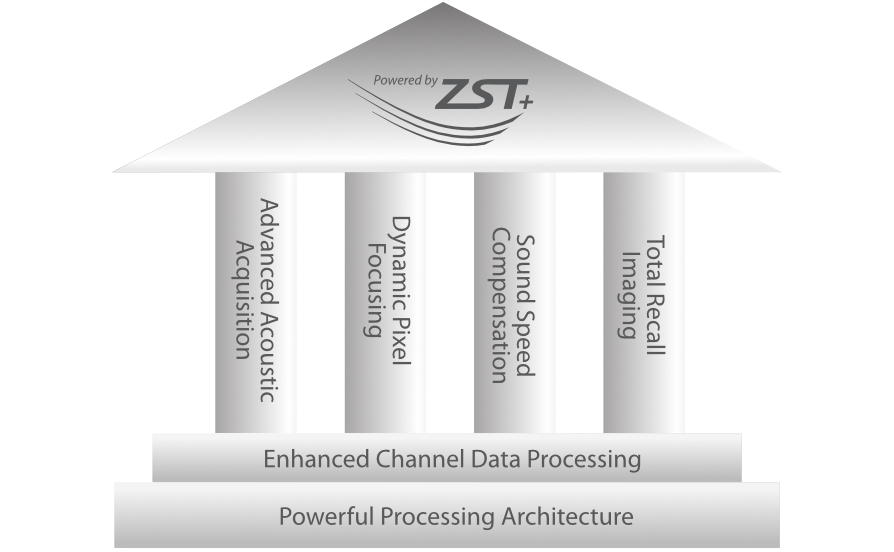

Con tecnologia ZST +

La piattaforma ZST+ rappresenta uno straordinario balzo in avanti nella tecnologia degli ultrasuoni, passando dal beamforming convenzionale all'elaborazione dei dati di canale. Questa innovazione rivoluzionaria supera i tradizionali compromessi tra risoluzione spaziale, risoluzione temporale e uniformit├Ā dei tessuti, dando vita a una qualit├Ā d'immagine senza pari che consente infinite soluzioni di imaging.